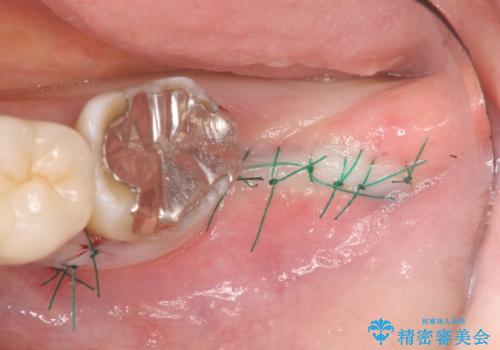

今後の機能回復方法としてインプラント治療を希望されたため、将来的に大規模な骨造成が必要とならないよう歯槽堤保存術を抜歯と同時に行いました。

良好なインプラントの植立を行うためには、十分な骨量があることが必須条件です。

術前、歯の破折により大きな骨の吸収が認められていたため骨量を十分に回復するために抜歯と同時に歯槽堤保存術を行い十分な骨量の回復をすることができました。